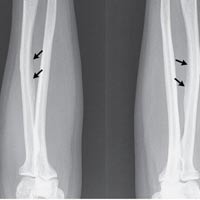

Những vùng xương mà flour trập trung quá nhiều, gây đau đớn

Kết quả chụp X-quang cho thấy mật độ xương ở cột sống rất cao và dây chằng ở tay bị vôi hóa, TS. Sudhaker D. Rao, nhà nghiên cứu nội tiết, xương và trao đổi chất ở bệnh viện Henry Ford, cho biết.

Các nhà nghiên cứu ngờ rằng người phụ nữ đã bị nhiễm độc flour ở xương do tiêu thụ quá nhiều khoáng chất flour (thường có trong trà và nước uống).

Máu của bệnh nhân có lượng flour cao gấp 4 lần bình thường.